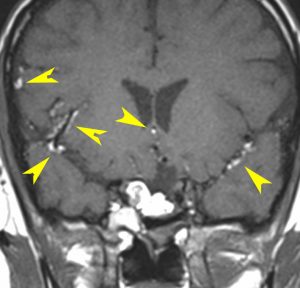

頭痛と嘔吐という髄膜刺激症状で発症しました。鞍結節部の類皮のう胞が破れたものです。黄色い矢印の先の白い点々にみえるのが散らばった内容物です。油滴です。